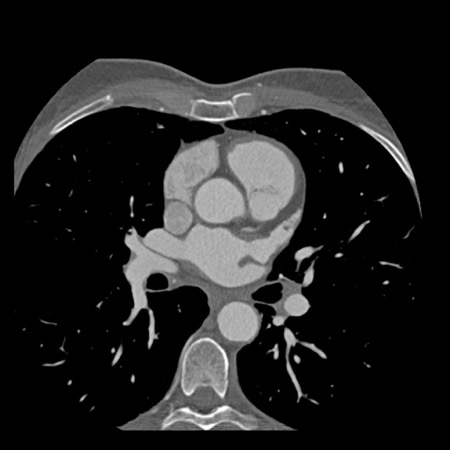

Continue with the next images of the same patient…

Same patient. First, study the CTA image.

How would you describe the findings?

The coronal image shows a central low-attenuation area around the lumen

of the LAD.

This low-attenuation area is surrounded by a higher attenuation

area.

This finding is the earlier discussed napkin-ring sign, which is a high-risk

plaque feature.

This patient classifies as CAD-RADS 4A/P1/HRP.